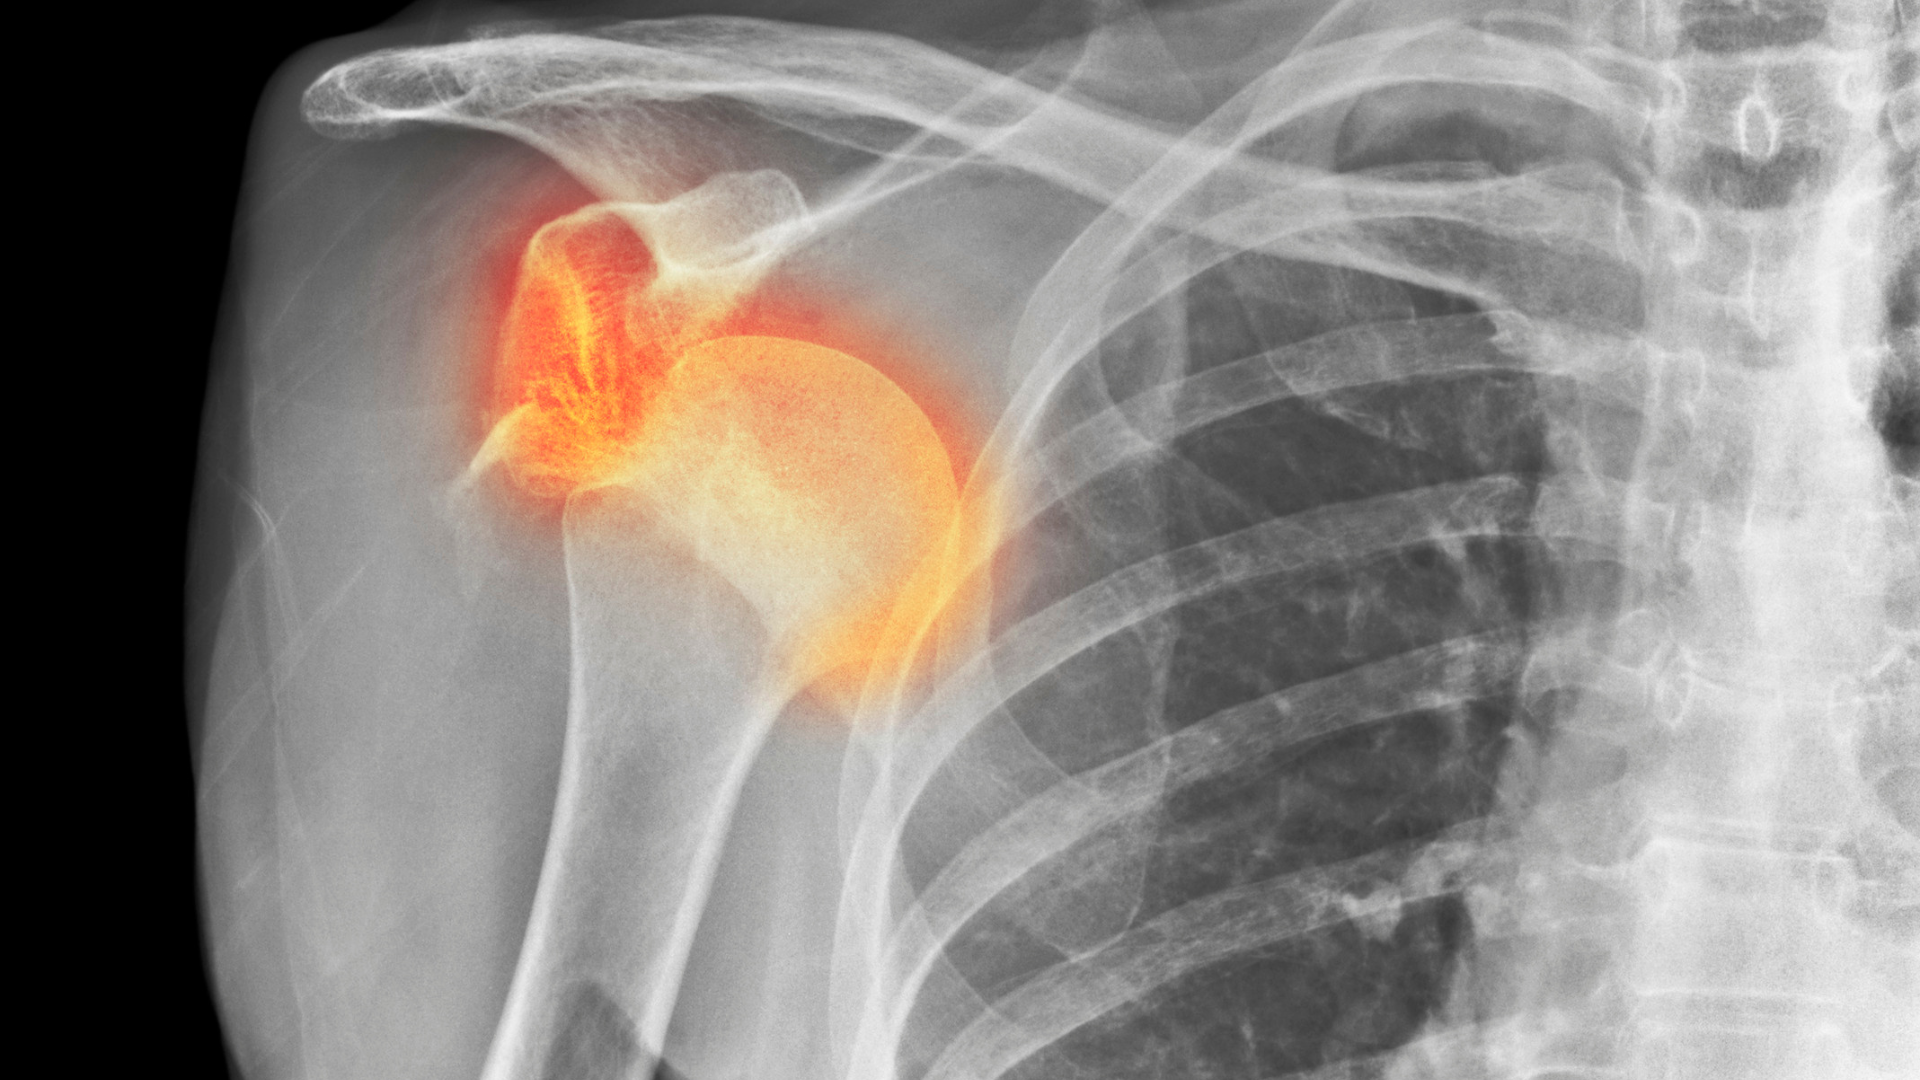

A luxação do ombro é uma das lesões mais comuns e dolorosas que afetam a articulação. Ela ocorre quando a cabeça do úmero (osso do braço) sai da cavidade glenoidal (articulação do ombro), causando dor intensa, inchaço e incapacidade de movimentar o braço. Se você já sofreu uma luxação ou quer saber como agir em caso de emergência, continue lendo para entender as causas, sintomas e tratamentos disponíveis.

A luxação do ombro é uma lesão traumática que ocorre quando a articulação do ombro é forçada a sair de sua posição normal. Essa articulação é a mais móvel do corpo humano, o que a torna mais suscetível a luxações. Existem dois tipos principais de luxação:

- Luxação Anterior: A mais comum, ocorre quando a cabeça do úmero se desloca para frente.

- Luxação Posterior: Menos comum, ocorre quando a cabeça do úmero se desloca para trás.